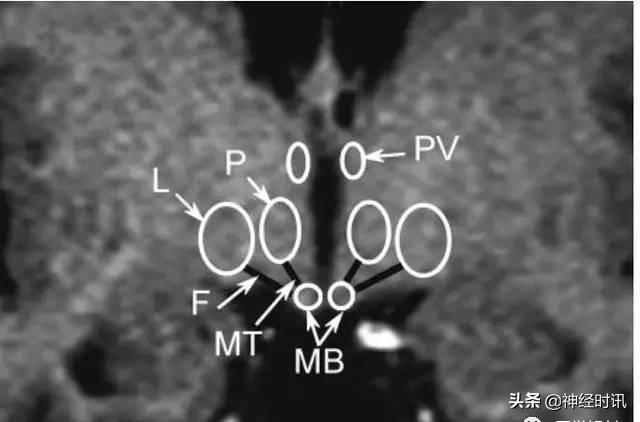

颅脑冠状面MRI表现

A:弓状核;AC:前联合;DM:背内侧核;L:外侧核;LPO:视前外侧核;MB:乳头体;MPO:视前内侧核;P:后核;OT:视束;OC:视交叉;SC:视上核;F:穹窿;PV:室旁核